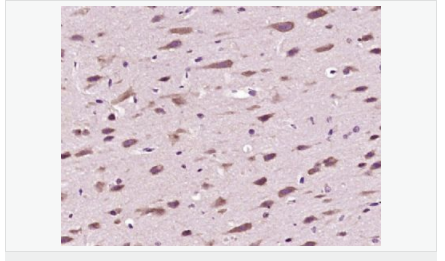

交叉反應(yīng):Human,Mouse,Rat(predicted:Pig,Cow,Horse,Rabbit) 推薦應(yīng)用:IHC-P,IHC-F,IF,ELISA

產(chǎn)品應(yīng)用ELISA=1:5000-10000 IHC-P=1:100-500 IHC-F=1:100-500 IF=1:100-500 (石蠟切片需做抗原修復(fù))

產(chǎn)品介紹The enzymes responsible for the reversible acetylation/ deacetylation process of histones are histone acetyltransferases (HATs) and histone deacetylases (HDACs), respectively. HATs act as transcriptional coactivators and HDACs are part of transcriptional corepressor complexes. Mammalian HDACs can be divided into three classes according to sequence homology. Class I consists of the yeast Rpd3 like proteins HDAC1, HDAC2, HDAC3, and HDAC8. Class II consists of the yeast Hda1 like proteins HDAC10, HDAC5, HDAC6, HDAC7, HDAC9, and HDAC10. Class III comprises the yeast Sir2 like proteins. Whereas class I HDACs are ubiquitously expressed, most class II HDACs are tissue specific. HDAC10 is similar to HDAC6, both containing a unique putative second catalytic domain not found in other HDACs. However, this domain is not functional in HDAC10. The deacetylase activity of class II HDACs is regulated by subcellular localization. HDAC10 was localized to both the nucleus and cytoplasm. HDAC10 can deacetylate histones, repress transcription, and interact with HDAC3.